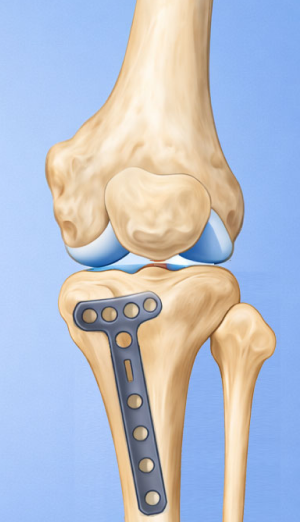

High Tibial Osteotomy (HTO)무릎 아래 뼈인 경골(정강이뼈)의 윗부분(근위부)을 절골하여 다리 정렬을 바로잡는 무릎 교정 수술입니다.

무릎 안쪽 관절이 닳아 O자 다리 형태로 휘어 통증이 생기는 경우, 다리의 축을 바로잡아 무릎 안쪽의 하중을 줄여주는 교정 수술입니다.

관절면과 평행하게 절골하여 각도를 교정

정강이 위쪽 뼈(경골 근위부)를 절골합니다.

약간 벌리거나 닫아서 다리축을 “일자에 가깝게” 교정해서 닳은 안쪽 무릎의 부담을 줄이고 통증 감소 및 기능 향상을 유도합니다.

절골한 부위는 금속판(plate)으로 고정합니다.